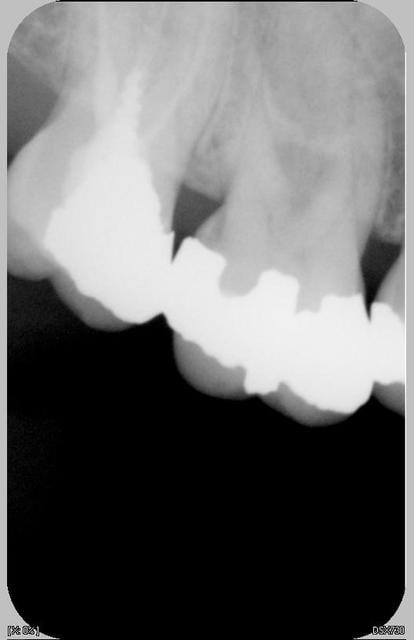

La série. Trois urgences différentes avec a priori un problème similaire.

Dans les trois cas , nuit difficile

Douleur à la pression localisée sur un dent particulièrement. Pas douleur au froid. Douleur au chaud et évidemment à la percussion.

Pas de gingivite autour de la dent si ce n'est ponctuellement en vestibulaire. La sonde pénétre nettement en interradiculaire unique siège de la douleur pour les 3 dents et uniquement en interradiculaire pour la radio 1 et 3.

J'ai désinfecté localement bain de bouche et ultrason. Je ne sais pas comment éliminer surement le problème (surtout pour 1 : bridge complet réalisé il y a un an sans problème jusqu'à maintenant)

Les radios 1, 2 et 3 sont ici

venal pour la 1 il faut voir au niveau de la furcation,dernierement j'ai eu un cas proche de celui ci radiologiquement mais sur une mol sup et ça s"est exprimé par une fistule vest au bout de qq semaines d'interrogations j'ai alors hemisectionné(il s'agit d'une 26 amputation racine vest mes) et mis à jour une lesion granulomateuse interadiculaire ++